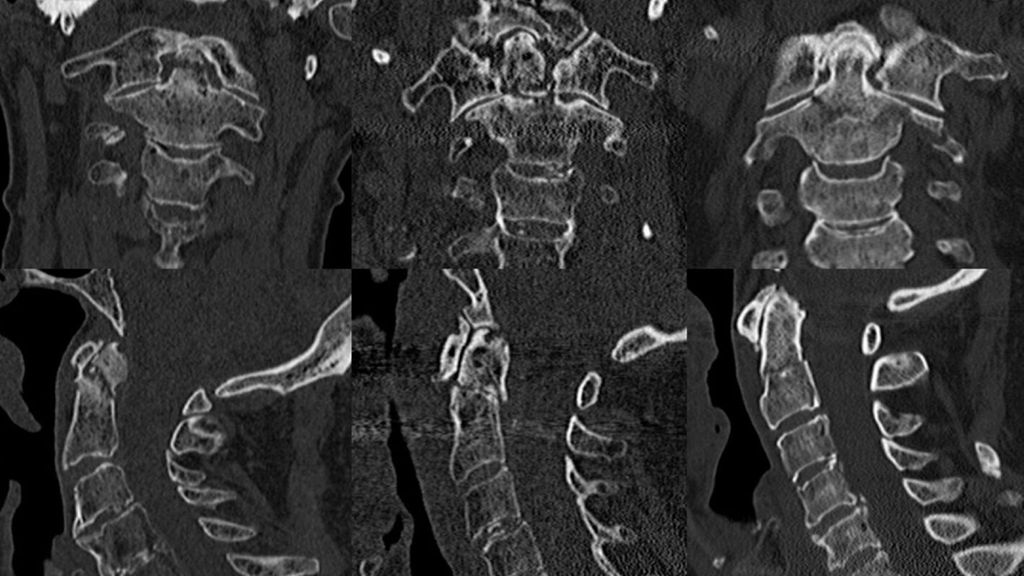

Die posteriore atlantoaxiale Fusion ist zwar invasiver, liefert jedoch bessere chirurgische Ergebnisse hinsichtlich der Frakturheilung und der Notwendigkeit von Revisionen bei höherer Primärstabilität.42 Bei geriatrischen Patienten über 75 Jahre36 wird bei Entscheidung zur Operation eine C1-C2-Arthrodese von dorsal empfohlen.26 Von den posterioren Fusionen am häufigsten durchgeführt werden die 2-Schrauben-Technik nach Magerl und Seeman und die 4-Schrauben-Technik nach Goel und Laheri bzw. Harms und Melcher. Beide erreichen hohe Fusionsraten und gute Stabilität. Zusätzlich zu den Verschraubungen kann auch eine Cerclage nach Gallie/Brooks angelegt werden, um die Stabilität noch zu verbessern (Abb. 2).34

Abb. 2: Post-OP-Röntgenbilder a.p. (obere Reihe) und seitlich (untere Reihe); transartikuläre Verschraubung nach Magerl (links), ventrale Verschraubung mit 2 Schrauben (Mitte) und mit 1 Schraube (rechts oben), Cerclage (rechts unten)